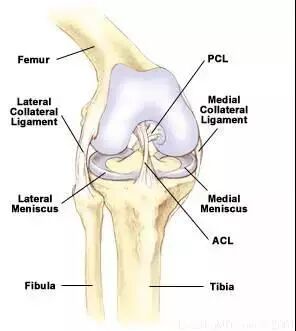

2、内侧副韧带损伤

①损伤时剧烈的用力外翻旋转(即激素的损伤使 猛推向内侧);

②内侧疼痛及压痛点在内侧副韧带(MCL)上;

③极微局限的渗出液(变异的)在内侧副韧带上(大量伴生的渗出液,则暗示合并有关节内部损伤,如前交叉韧带(ACL)或后交叉韧带(MCL);

④在膝盖弯曲30度时的外翻加压测试时疼痛或可打开空隙,则具有第二或第三型内侧副韧带损伤。

14、前十字韧带撕裂

①急性伤害(伸直过度、外翻剪力等);

②急速的渗出液(在伤害以后少于2小时)暗示着关节血肿是由于被撕裂的韧带末端流血的结果;

③无法继续运动;

④主观的不稳;

⑤阳性的Lachman测试,枢轴移动测试;

⑥阳性的前抽屉试验(较Lachman测试不敏感和特定)。

16、后十字韧带撕裂

①异常的后抽屉测试;

②PCL的伤害机制;

③渗出液;

④后坠症状。